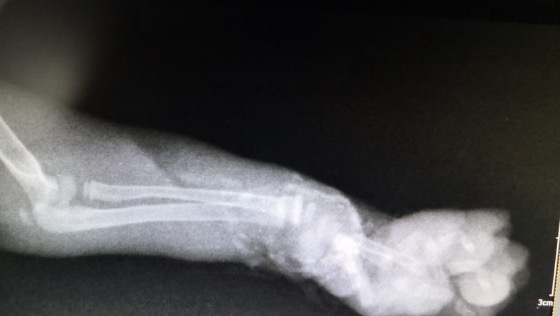

Pewne dobre osoby w drodze do domu zauważyły skulone przy krawężniku, na ulicy małe kociątko. Zwierzak był wystraszony i nie mógł się poruszać. Natychmiast zabrały malucha do weterynarza, ponieważ biedaczek miał zmiażdżoną łapkę...zapewne ktoś potrącił kota i nie raczył się zatrzymać, aby udzielić mu pomocy. Gdyby nie reakcja ludzi, maluch zapewne umarłby gdzieś samotnie w krzakach albo na jezdni.

Po konsultacji z lekarzem okazało się, że konieczna będzie amputacja kończyny. Zdecydowaliśmy się pokryć koszty operacji, bo biedactwo zasługuje na normalne życie.